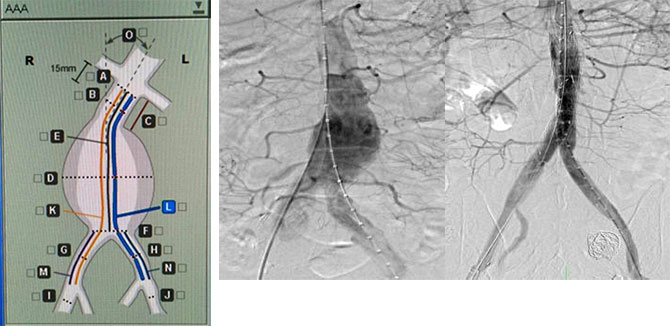

3. 腔内治疗:腹主动脉瘤腔内修复术是治疗腹主动脉瘤的微创手术方式,其特点是创伤小,避免了传统手术所带来的巨大创伤和痛苦,降低了病人心、肺等重要脏器并发症的发生率和死亡率,尤其对于一些有严重合并症、预期不能耐受传统开腹手术或手术后可能出现严重并发症的高危病例提供了治疗的机会。随着“开窗技术”、“烟囱技术”等的成熟和带分支支架及多层支架的出现,使得越来越多原本需要行开腹手术治疗的复杂腹主动脉瘤倾向于腔内治疗。另外,对于某些累及内脏动脉而不适合行腔内治疗,且合并其他严重疾病不能行开放手术治疗的患者,为了减少手术创伤,为微创腔内修复手术创造条件,可应用联合开放手术和腔内修复术的杂交技术来治疗。